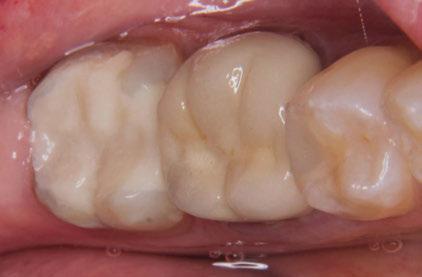

Ramos-Ríos y cols. estudiaron dos escuelas con niños de rango de edad de 6 y 12 años, en México. Para ello, se empleó un cuestionario para los padres y se obtuvo que un 6,84% padecían asma; de éstos se llevó a cabo el estudio (Tabla 1).

Tras los resultados obtenidos llegaron a la conclusión de que son muchas las patologías asociadas al asma, y no solo repercusiones sobre su salud oral, sino maloclusiones del tipo mordida abierta o paladar ojival asociadas a deglución atípica, propias de una respiración oral

también relacionada con esta patología. El pH ácido se encontró en un 96,42% de los niños y se sabe que tiene relación directa con la formación de caries. No encontraron asociaciones con xerostomía, erosión dental o candidiasis, siendo estas patologías relacionadas, al mismo tiempo, con la inmunosupresión generada por los fármacos (1).

Samec y cols. afirmaron la existencia de asociación directa entre aparición de caries y el empleo diario de glucocorticoides inhalados, ya que pasados los 3 años el incremento de lesiones cariosas fue significativamente superior en los niños asmáticos frente a sus hermanos sin patología (6).

Domenzain-Sanchez y cols. realizaron un estudio transversal de casos y controles con pacientes de 5 a 12 años. Un 80% de los asmáticos presentaban caries, a pesar de que los autores no encontraban relación directa entre caries y enfermedad asmática. Éstos consideran que la medicación es la causa principal de las caries, ya que gran parte se queda en la orofaringe, además de reducir el flujo salival y tener azú cares. Los niños asmáticos tienen 1,02 mayor riesgo de erosión dental que los niños no asmáticos; esto se debe a la acidez de los fármacos que reducen el pH y provocan reflujo gastroesofágico. La mayoría de los estudios no avalan una asociación directa con el bruxismo, ya que en niños es muy frecuente, pero concretamente

en este estudio resultó que un 14% presentaban bruxismo dentro del grupo de asmáticos y lo justifican con la obstrucción parcial prolongada o completa de las vías respiratorias (53).

Gorji y cols. realizaron un metaanálisis para establecer la asociación entre caries y asma. Llegaron a la conclusión de que el asma es un factor de riesgo de caries y de no tratarse adecuadamente y tener las medidas preventivas necesarias, aumenta la probabilidad de desarrollar caries. Atendiendo a la falta de suministro de oxígeno, los ameloblastos se ven afectados y se altera la formación del esmalte, lo que origina defectos sin posibilidad de reparación como el MIH o síndrome de hipomineralización incisivo-molar (9).